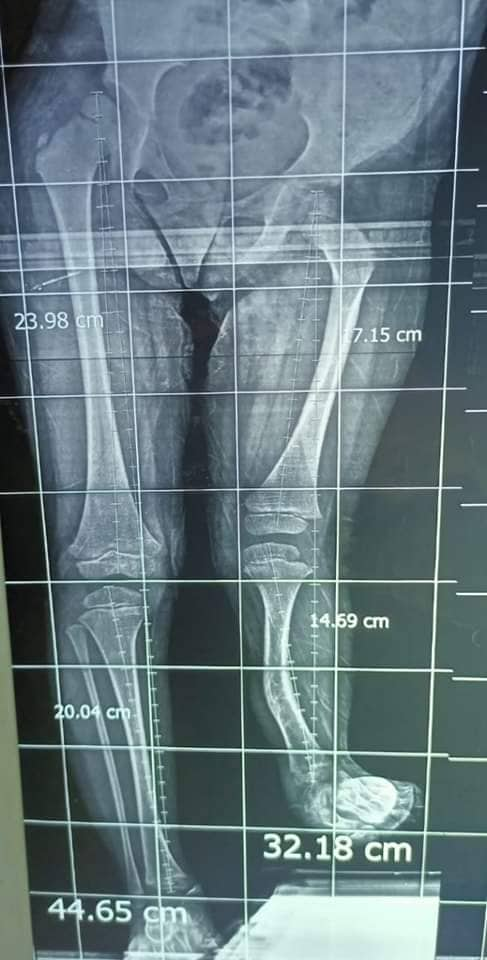

نجح الفريق الطبي بقسم جراحة العظام بمستشفى ديرب نجم المركزي، محافظة الشرقية بقيادة الدكتور شريف محمود رئيس قسم العظام، وبإشراف الدكتورمحمد العوضي مدير المستشفى، في إجراء عملية جراحية ذات مهارة لطفلة تبلغ من العمر 4 سنوات، تعاني من قصربعظمة الساق بالطرف الأيسريبلغ 13 سم، نتيجة لعيب خلقي.

وتم عمل إطالة للعظمة باستخدام مثبت خارجي "اليزاروف" وذلك مجانًا بقرارعلاج تابع للتأمين الصحي يتخطي 25 ألف جنيه، وبعد إجراء كافة الفحوصات المعملية والأشعات اللازمة، والمريض الآن بحالة جيدة ومستقرة تحت متابعة الفريق الطبي بالمستشفى.